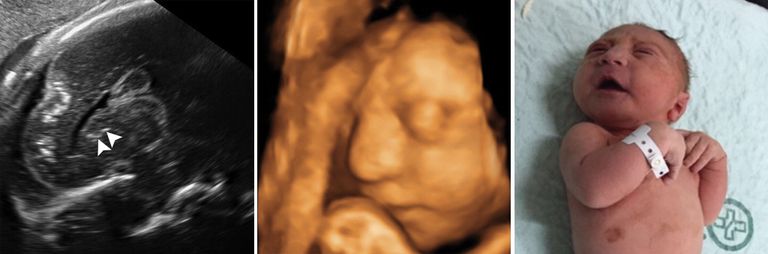

وقالت الصحيفة، إن دراسة صور الأشعة على المخ، وصور الموجات فوق الصوتية لـ 45 طفلًا برازيليًّا أصيبت أمهاتهم بالفيروس خلال فترة الحمل تبين أنه يمكن أن يلحق أضرارًا جسيمة بعدة أجزاء مختلفة من مخ الجنين أكثر من مجرد تشوه الرأس، وهي حالة صغر الرأس غير المعتادة التي أصبحت بمثابة العلامة الخبيثة لـ"زيكا".

ويقول الخبراء، إن معظم الأطفال الذين شملتهم الدراسة ولدوا بتشوه الرأس، على الرغم من أن 3 لم يصابوا به، وكل منهم عانى تشوهات أخرى أيضًا، تظهر كلها تقريباً قبل صغر الرأس لأنه في الحقيقة نتيجة فشل الدماغ في النمو بشكل كامل أو تعرضه لأضرار على نحو مستمر.

من جانبها قالت الطبيبة ديبورا ليفين، وهي مؤلفة الدراسة وأستاذة الأشعة في كلية الطب بجامعة هارفارد، إن "المخ الذي ينبغي أن يكون هناك ليس هناك، والتشوهات التي نراها في الدماغ تشير إلى اختلال في عملية نمو المخ في وقت مبكر للغاية".

وتظهر صور الأشعة أن أهداف "زيكا" في المخ، التي يعرف بعضها الخبراء، تشمل "الجسم الثنفي" وهو الجزء الذي يسهل التواصل بين شطري الدماغ، والمخيخ الذي يلعب دورًا هامًّا في الحركة والتوازن والكلام؛ والعقد العصبية القاعدية التي تشارك في التفكير والعاطفة.